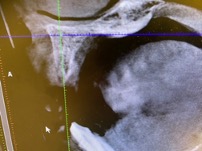

右上の前歯の歯周ポケットの深さを測ると1カ所だけ深く、レントゲンでも透過像があり、歯が破折している事を確認しました。噛み合わせが良くない影響で、歯が破折してしまったと考えられます。

その後CTで骨の状態を確認したところ、唇側の骨の量が少ない事がわかりました。インプラント埋入の際、骨が少ないと予後不良になりやすいため、患者様と相談し、骨造成(骨を作る処置)を行い、インプラントを埋入することとなりました。